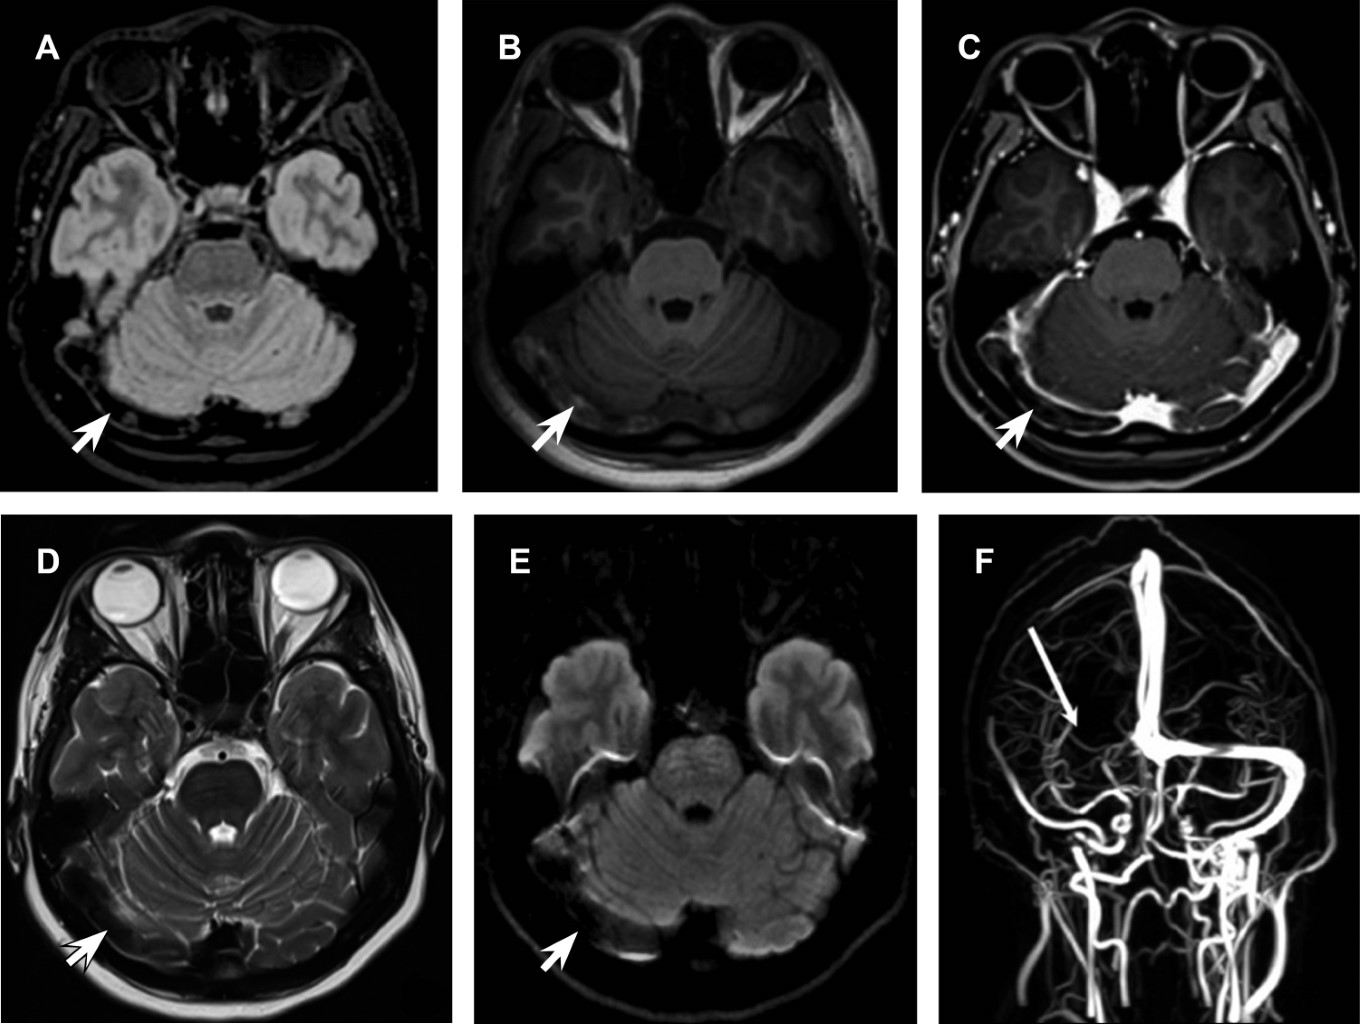

Una mujer de 27 años, con antecedentes de síndrome de ovario poliquístico y tratamiento con drosperinona/etinilestradiol, presentó cefalea punzante en la región temporal derecha irradiada hacia la órbita derecha, fotofobia y algiacusia. La tomografía y resonancia magnética demostraron falta de permeabilidad del sistema venoso del seno transverso, seno sigmoideo, golfos de la yugular derecha e hiperintensidad de los senos longitudinal superior, longitudinal inferior, vena de galeno, seno transverso, seno sigmoideo y golfo yugular en el lado izquierdo, relacionados con enlentecimiento del flujo (Figura 2). Se indicó manejo con enoxoparina y posteriormente rivaroxavan 20 mg/día, presentando mejoría clínica.

La neurorradiología juega un papel vital en la identificación y tratamiento de la TVC. La RM con venografía, una técnica no invasiva, ofrece una visualización detallada de los vasos cerebrales y el parénquima cerebral asociado. En el caso clínico, la RM reveló falta de permeabilidad en varios senos venosos cerebrales e hiperintensidad en otros, lo que facilitó el diagnóstico y tratamiento temprano.

Figura 2